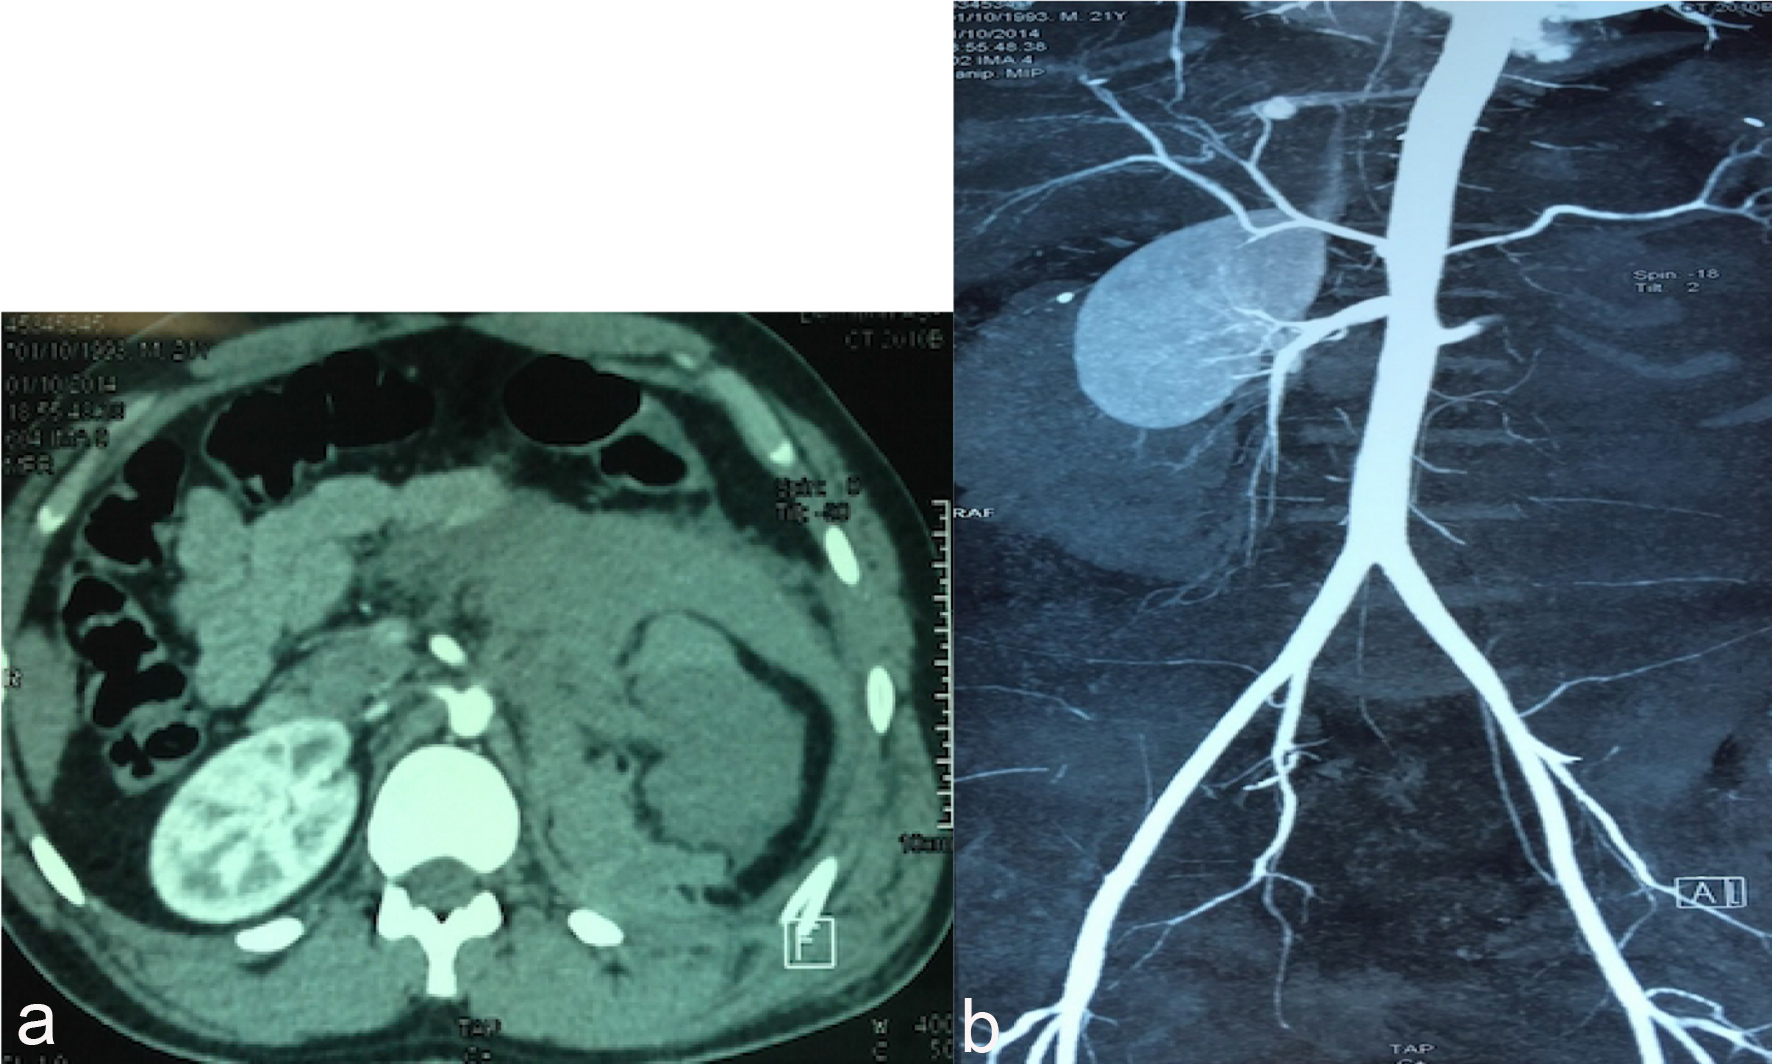

After conditioning, an abdominal CT scan was performed and revealed a rupture of the left renal artery a few millimeters from its origin, with a silent left kidney and a large retro-peritoneal hematoma that fuse behind the lesser omental sac without extravasation of the contrast dye (Fig. 1). In addition, the patient had splenic contusion and a complex fracture of the eleventh left rib.

![]() Click for large image | Figure 1. (a) Scan of the day of the trauma; (b) angio-scanner: juxta aortic dissection lesion. |